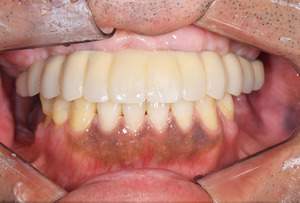

AFTER

| 年齢・性別 | 63歳・男性 |

|---|---|

| 主訴 | インプラントがしたい |

| 治療内容 | オールオン4(上顎) |

| 治療費 | オペ料金(仮歯・薬代金含み)150万円+上部構造 (ハイブリットセラミック)150万円=計300万円(消費税別) |

| 治療期間 | 7ヶ月 |

| リスク・副作用 | 治療後の口腔管理が不適切な場合、インプラント周囲に炎症が生じインプラントが脱落する恐れがある。 |

審美的にも、機能的にも調和がとれており何よりも食べ物がちゃんとかめると言う事に感激されておりました。 今後定期検診をしながら経過を診て行きたいと思い

ます。